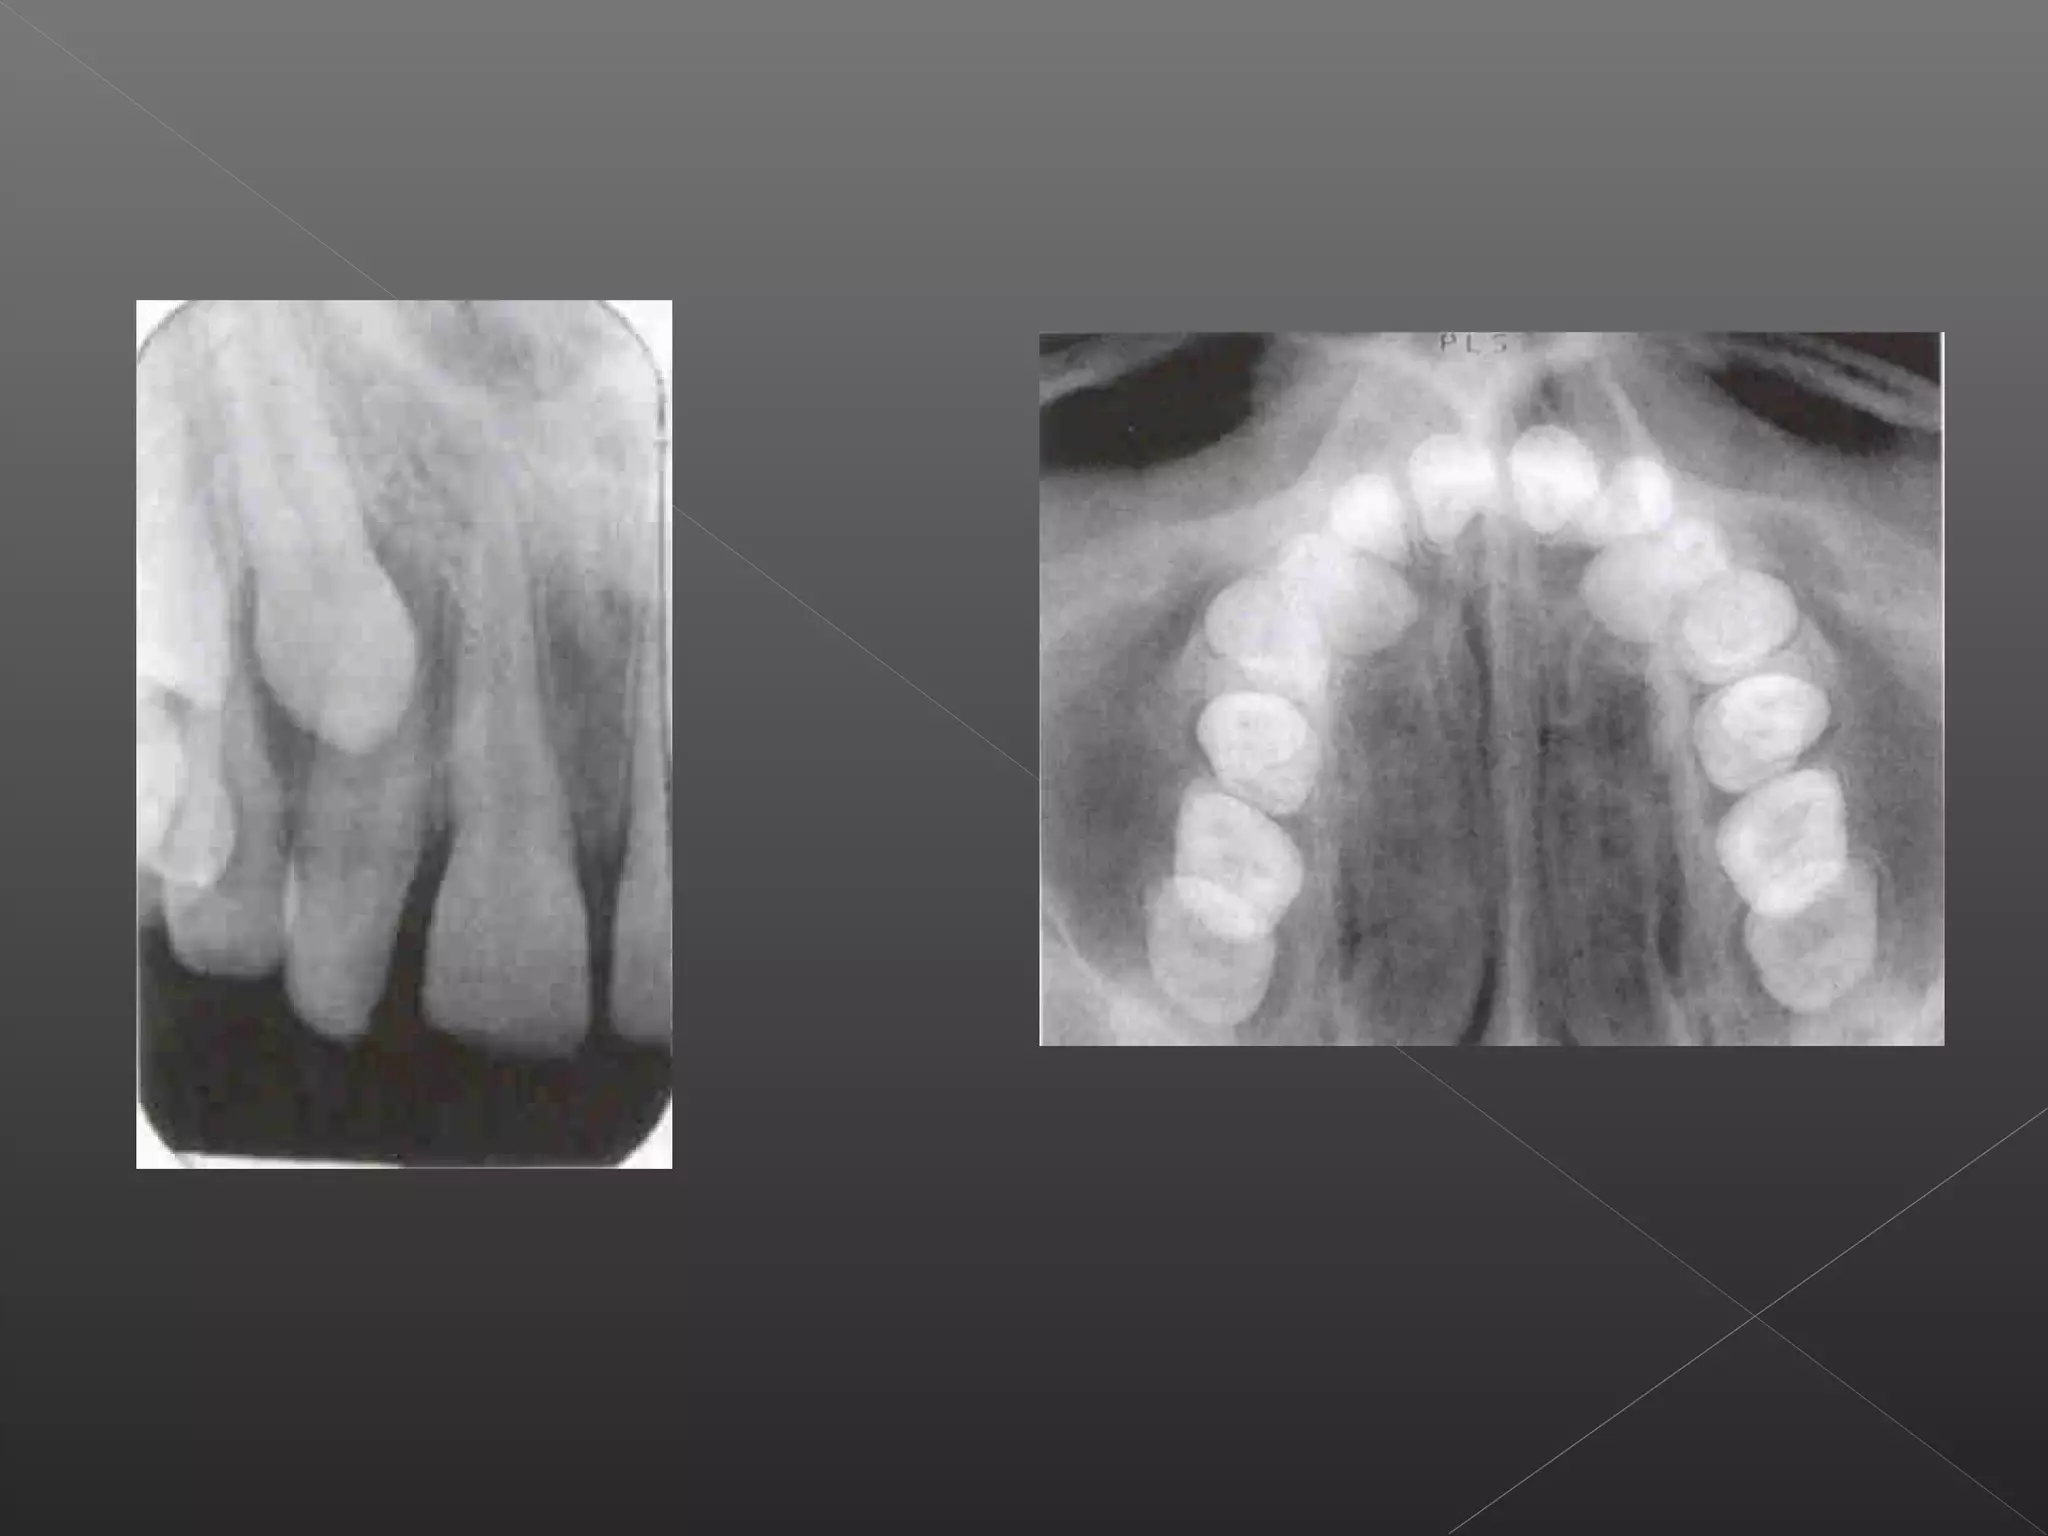

This document discusses techniques for localizing objects using radiography. It describes common reasons for needing to localize foreign bodies or other objects like unerupted teeth, fractures, or tumors. Two main techniques are described: Miller's technique which uses two radiographs at right angles, and Clark's tube-shift technique which analyzes how an object's image shifts when the projection angle is changed. The advantages and disadvantages of each technique are provided.